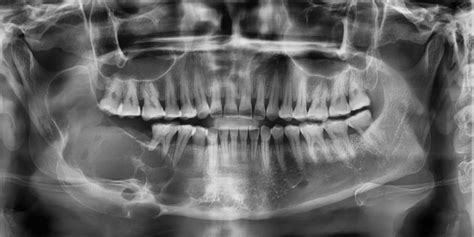

- Pruebas de imagen: Para afinar el diagnóstico, casi siempre usamos alguna imagen. La ecografía (ultrasonido) del área submandibular es muy útil: es rápida, indolora y nos dice si el bulto es sólido o lleno de líquido, su tamaño exacto y características internas. Con una eco podemos distinguir bastante bien un ganglio linfático (tiene cierta forma y ecotextura característica) de un quiste (lesión líquida) o de un tumor sólido. Si persiste duda, pasamos a estudios más detallados: una radiografía panorámica dental detectará si hay lesiones óseas o abscesos dentales ocultos; una Tomografía Computarizada (TAC) o Resonancia Magnética (RMN) nos dará una imagen más precisa de la ubicación del bulto, su relación con estructuras vecinas y sospecha de naturaleza. Por ejemplo, ante un quiste mandibular grande, el TAC mostrará la cavidad en el hueso; ante un tumor de glándula, la RMN delineará sus bordes y extensión.